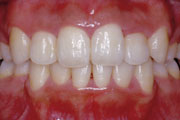

一般矯正の症例

症例1:乱杭歯(叢生)